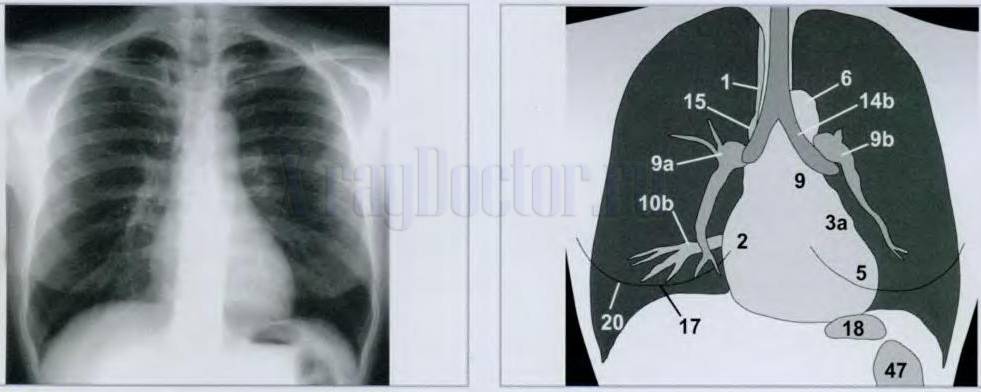

Нормальная рентгенограмма легких: что нужно знать

Раздел: Мудрость в объективе